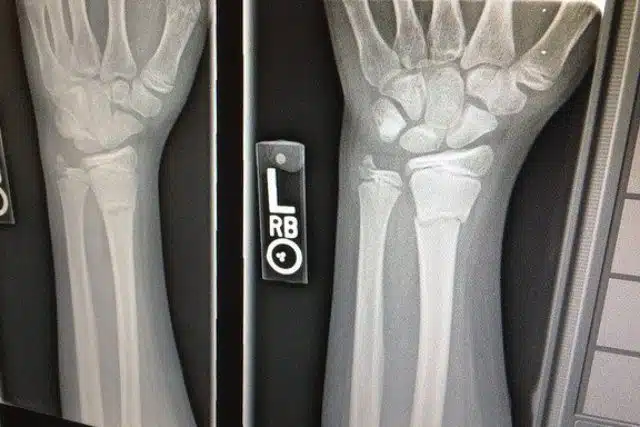

- Wrist and Thumb Injuries: “Skier’s thumb,” involving the ulnar collateral ligament, arises when someone lands on an outstretched hand with a pole in grip, along with common distal radius fractures.